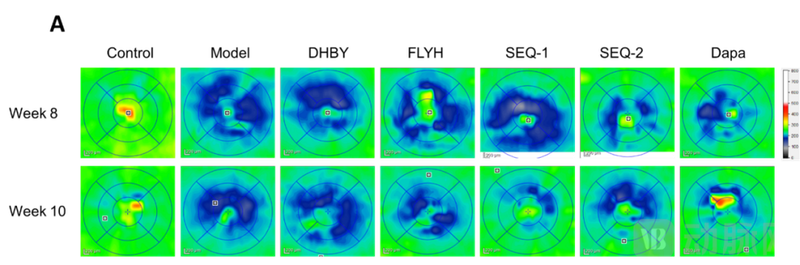

(视网膜OCT多线扫描图:蓝色区域越大、颜色越深代表视网膜厚度越薄)

OCT多线扫描图显示,与正常组比较,模型组视网膜厚度显著变薄。与模型组比较,序贯治疗8周序贯干预8周的视网膜厚度显著变厚:SEQ-2组给药干预8周的视网膜厚度显著变厚,SEQ-1组停药2周后的视网膜厚度显著变厚(P<0.05)。